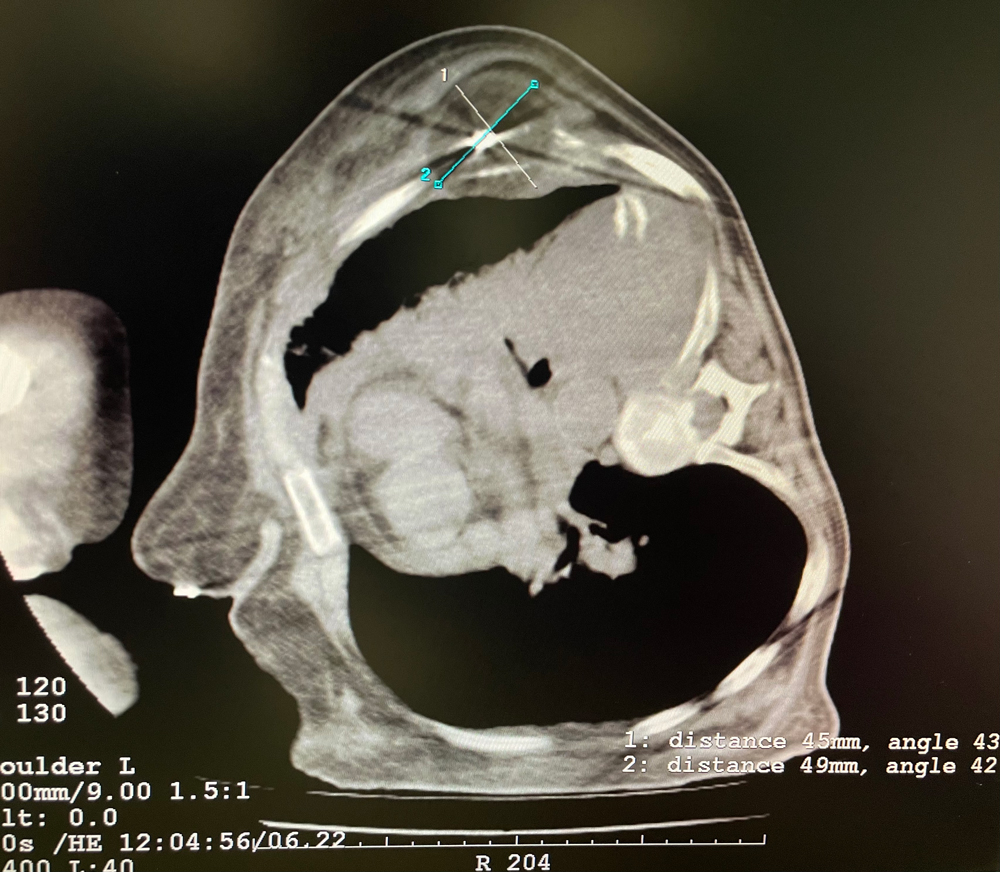

女,56歲,肺轉移瘤,骶骨、左側肋骨各一轉移灶,病灶大小均為5cm。骶骨轉移灶、肋骨轉移灶各進行2個凍融循環(huán)。患者術后狀況良好。

女,42歲,復發(fā)性脂肪瘤,病灶位于右側膝關節(jié),直徑大小13cm。采用雙針方案,共進行6個凍融循環(huán),最大冰球直徑達8.2cm,術中多方位治療全面覆蓋病灶范圍。患者術后狀況良好。